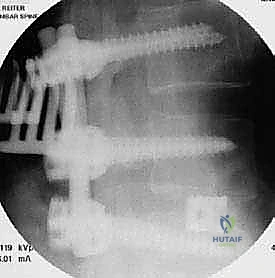

الخطوة 4: زراعة القفص والطعم العظمي (Cage Insertion)

يتم إدخال قفص مصنوع من مادة PEEK أو التيتانيوم، مملوء بطعم عظمي (يؤخذ غالباً من المريض نفسه أو طعم صناعي)، في المساحة الفارغة. هذا القفص يعيد الارتفاع الطبيعي للفقرات ويخفف الضغط عن منافذ الأعصاب.

يتم وضع المريض على بطنه. يتم عمل شق جراحي دقيق في أسفل الظهر. باستخدام أجهزة الملاحة الجراحية والأشعة السينية الحية (Fluoroscopy)، يتم تحديد المستويات الفقرية المستهدفة بدقة.